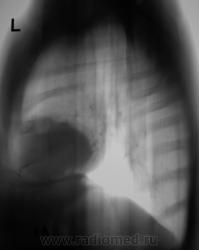

Либо целомическая киста перикарда, либо аневризма левого желудочка...

Не исключается и....

Слева на "зло" не похоже, но, что это конкретно, сказать не могу.

Уважаемые коллеги, а какие мысли насчет округлой тени в правом кардиодиафрагмальном углу (на уровне переднего отрезка 6-го ребра)?